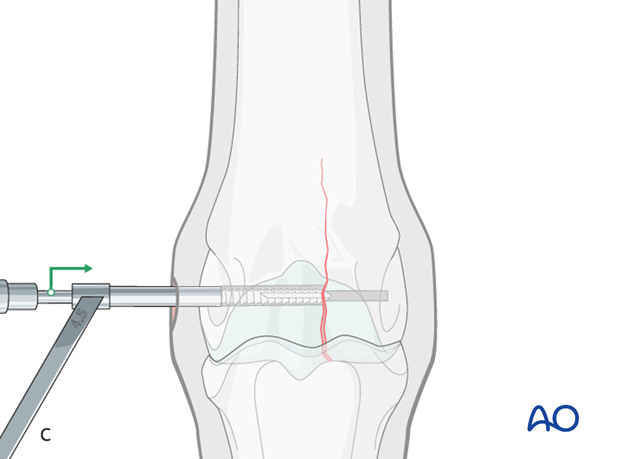

The screw is inserted but not fully tightened.

Ideally, a fluoroscopic view is taken to estimate if the screw length is correct. If correct, the screw is fully tightened. Some surgeons prefer to have the horse take weight off the limb while the final tightening is performed.